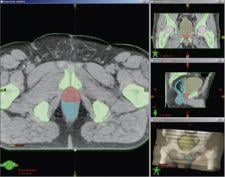

The new Smart Segmentation automatic contouring feature is reportedly the first fully automatic tool that uses intelligent software to identify and outline, within diagnostic images, organs and other structures to be irradiated or protected during treatment. The first version of the Smart Segmentation tool performs automatic contouring of tumors and surrounding anatomy in the thorax and in the male pelvis. Additional anatomical sites will be added in the near future.